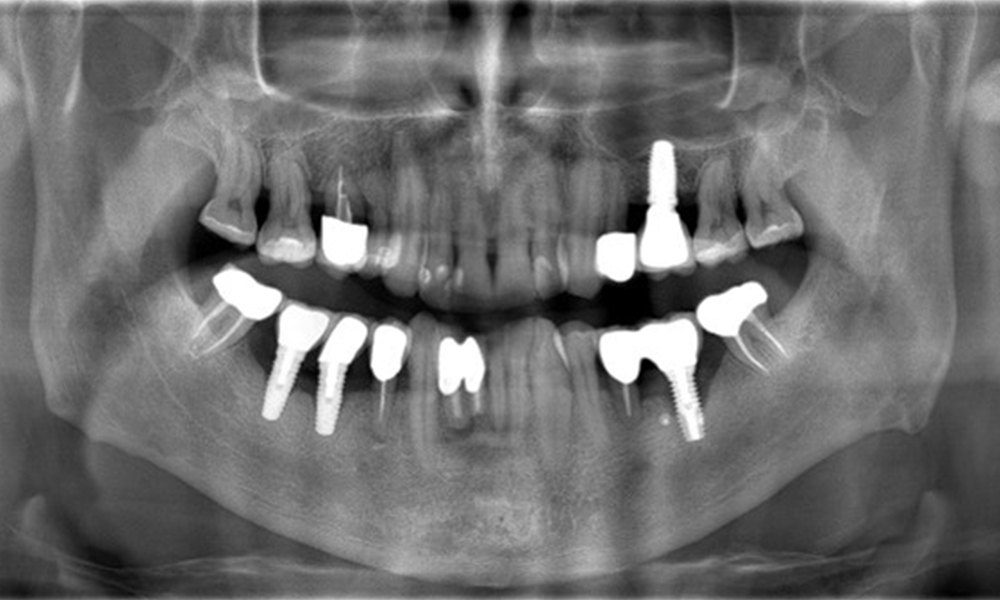

52-годишен пациент се явява на профилактичен преглед. Пациентът няма хронични заболявания и не приема никакви лекарства. Претърпял е различни дентални лечения и също така има две активни кариозни лезии. Освен това има четири импланта (2-ри, 3-ти и 4-ти квадрант). Установява се, че има ранно пародонтално заболяване (стадий IV, степен В). Състоянието на пародонта е стабилно, като дълбочина на сондиране (ST) от 5 mm се проявява само при импланта в област 36. Установен е и гингивит.

В историята на заболяването на пациента няма особени рискови фактори със специфични дентални последици. Следователно ключовият фактор е изискването по отношение на оралното здраве. В това отношение има данни за дълбочина на сондиране от 5 mm при импланта в 3-ти квадрант, а на рентгеновата снимка - за увеличена костна загуба. Пациентът също така има стабилно понастоящем пародонтално заболяване и две активни начални кариозни лезии.